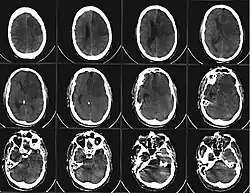

Компьютерная томограмма головного мозга, демонстрирующая инфаркт в правом полушарии головного мозга (зона инфаркта обведена красным.) | |

Магнитно-резонансная и компьютерная томография в диагностике ишемического инсульта

При остром периоде ишемического инфаркта мозга магнитно-резонансная томография (МРТ) является более эффективным методом ранней визуализации, чем компьютерная томография. На стандартных томограммах в 80 % наблюдений в первые 24 часа после развития окклюзии сосуда ишемические изменения уже становятся видимыми. При дополнительном введении контрастных препаратов в области ишемии отмечается контрастирование артериальных сосудов на Т1-взвешенных изображениях, что говорит о снижении в них скорости кровотока. Эти изменения могут развиваться уже в течение первых минут после окклюзии. Кроме того, к ранним МР-проявлениям относят изменения паренхимы мозга, выражающиеся в утолщении извилин и сужении субарахноидальных пространств на Т1-взвешенных томограммах, и повышение сигнала в режиме Т2. Эти изменения обычно выявляются не ранее чем через 8 часов после окклюзии[34]:347-348.

При компьютерной томографии (КТ) головы область гиподенсивности (пониженной плотности) у большинства больных выявляется через 12—24 ч с момента развития ишемического инсульта. При меньшей давности поражение не обнаруживается почти в половине случаев. Небольшие по размеру инфаркты мозга (инфаркты в мозговом стволе и лакунарные инфаркты) часто не дифференцируются на бесконтрастных КТ-изображениях даже на 3—4-й день заболевания (в период, когда инфаркты других локализаций визуализируются наилучшим образом), однако могут быть обнаружены при КТ с контрастированием. Проведение КТ с внутривенным контрастным усилением также показано в неясных случаях для дифференциальной диагностики[35].

В течение первых 3 суток развития инфаркта мозга на МРТ с контрастированием примерно в 30 % случаев может наблюдаться усиление сигнала от соседней твёрдой мозговой оболочки. Однако в 10—20 % наблюдений МР томография не выявляет каких-либо патологических изменений. Магнитно-резонансная ангиография выявляет окклюзию или выраженный стеноз в основном крупных артериальных стволов[34]:348.

В последние годы появились новые диагностические возможности определения ишемических повреждений в максимально ранние сроки. К ним можно отнести транскраниальную доплерографию, МР-спектроскопию, диффузионные и перфузионные МР-исследования[34]:348.

В подостром периоде ишемического инсульта происходят дальнейшие изменения. В течение первых 2—4 дней начинает уменьшаться и может совсем исчезнуть внутриартериальное и менингеальное контрастное усиление. Вслед за этим начинает выявляться паренхиматозное контрастирование за счёт усиливающегося повреждения гемато-энцефалического барьера. Контрастное усиление на 3—4 сут имеет типичную картину, повторяющую конфигурацию извилин, сохраняясь иногда до 8—10 нед[34]:348-349.

Отёк в зоне ишемии проявляется снижением сигнала на Т1-взвешенных и повышением сигнала на Т2-взвешенных изображениях. Иногда в течение второй недели после начала инфаркта отмечается снижение интенсивности сигнала на Т2-взвешенных томограммах. Начально высокий сигнал может даже полностью исчезнуть. Тем не менее, выполнение в эти сроки МР-томографии с контрастным усилением выявляет обширные поля накопления контраста, даже в тех зонах, которые представляются абсолютно интактными на Т2-изображениях[34]:349.

В хроническом периоде ишемического инфаркта на КТ и МРТ в бассейне окклюзированного сосуда определяется хорошо отграниченная зона энцефаломаляции, имеющая плотность на КТ и сигнал на МРТ, приближающийся по характеристикам к ликвору. Отмечается расширение расположенных по соседству субарахноидальных щелей мозга и соответствующего участка желудочковой системы с подтягиванием прилежащих её отделов к зоне поражения мозгового вещества. Контрастное усиление мозгового вещества, как правило, исчезает через 8—10 недель после развития заболевания[34]:349.

Лакунарные инфаркты имеют округлую форму, низкий сигнал на Т1-взвешенных и повышенную интенсивность сигнала на Т2-взвешенных томограммах. Имеют характерное расположение в глубоких отделах мозга[34]:349-350.